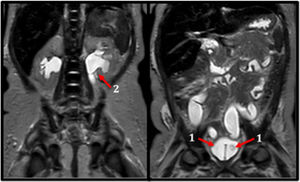

A PHA-1 was suspected. An abdominal ultrasound was done revealing bilateral intravesical ureteroceles and secondary uretero-pyelocaliceal dilatation. Diagnosis was confirmed with magnetic resonance imaging (MRI), micturating cystourethrography (MCU), and renogram (Fig. 1). Later, a genetic study ruled out primary PHA-1.

Initial stabilisation includes cardiac membrane protection with calcium gluconate, volume resuscitation and electrolyte correction under continuous cardiac monitoring. For this, it is usually necessary to transfer to the PICU.2,3 In the first hours, the differential diagnosis should include measurement of serum electrolytes and acid-base balance, and later, plasma renin activity, aldosterone levels, and cortisol. In PHA-1, plasma renin and aldosterone levels are markedly elevated, while cortisol levels are normal, distinguishing it from CAH.5 Added to this, imaging tests such as abdominal ultrasound or MRI could be useful to detect surgically treatable causes (Fig. 1).